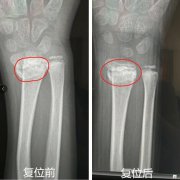

人民网重庆1月8日电 本来以为复位后就好了,没想到过了一段时...